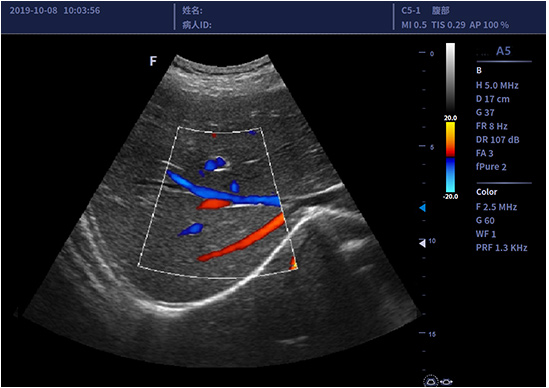

• C5-1/C5-2凸阵探头

适用于腹部、妇产、泌尿等

临床超声检查